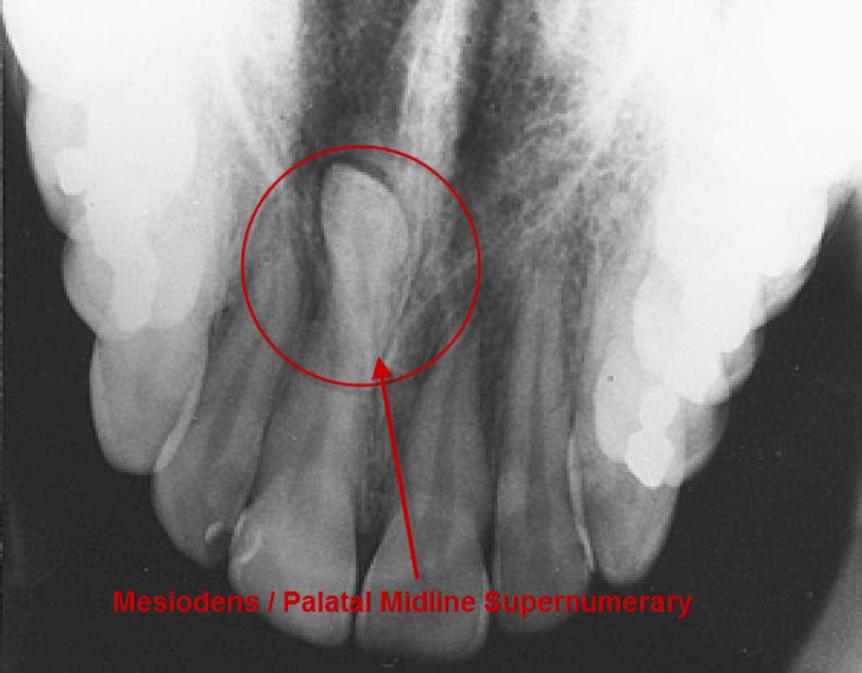

The prevalence of supernumerary teeth is reportedly between 0.15 – 3.9%. Most commonly, extra teeth are found between the upper central incisors (mesiodentes) or in the region of the premolars (paramolars) or very occasionally, behind the wisdom teeth (distomolars).

80 – 90% of all supernumerary teeth occur in the upper jaw. Half are found at the ‘front’ of the upper jaw. Mesiodentes frequently interfere with the eruption and alignment of the upper incisors. They can delay or prevent eruption, displace or rotate the erupting central incisors or less commonly, ‘bend’ (dilaceration) the developing roots of the central incisors so that tooth eruption is slowed / stopped, ‘eat away’ (resorption) the surrounding teeth, develop cysts around the crowns of the extra teeth (dentigerous cyst formation) and loss of tooth vitality. Rarely, the mesiodens can erupt into the nasal cavity